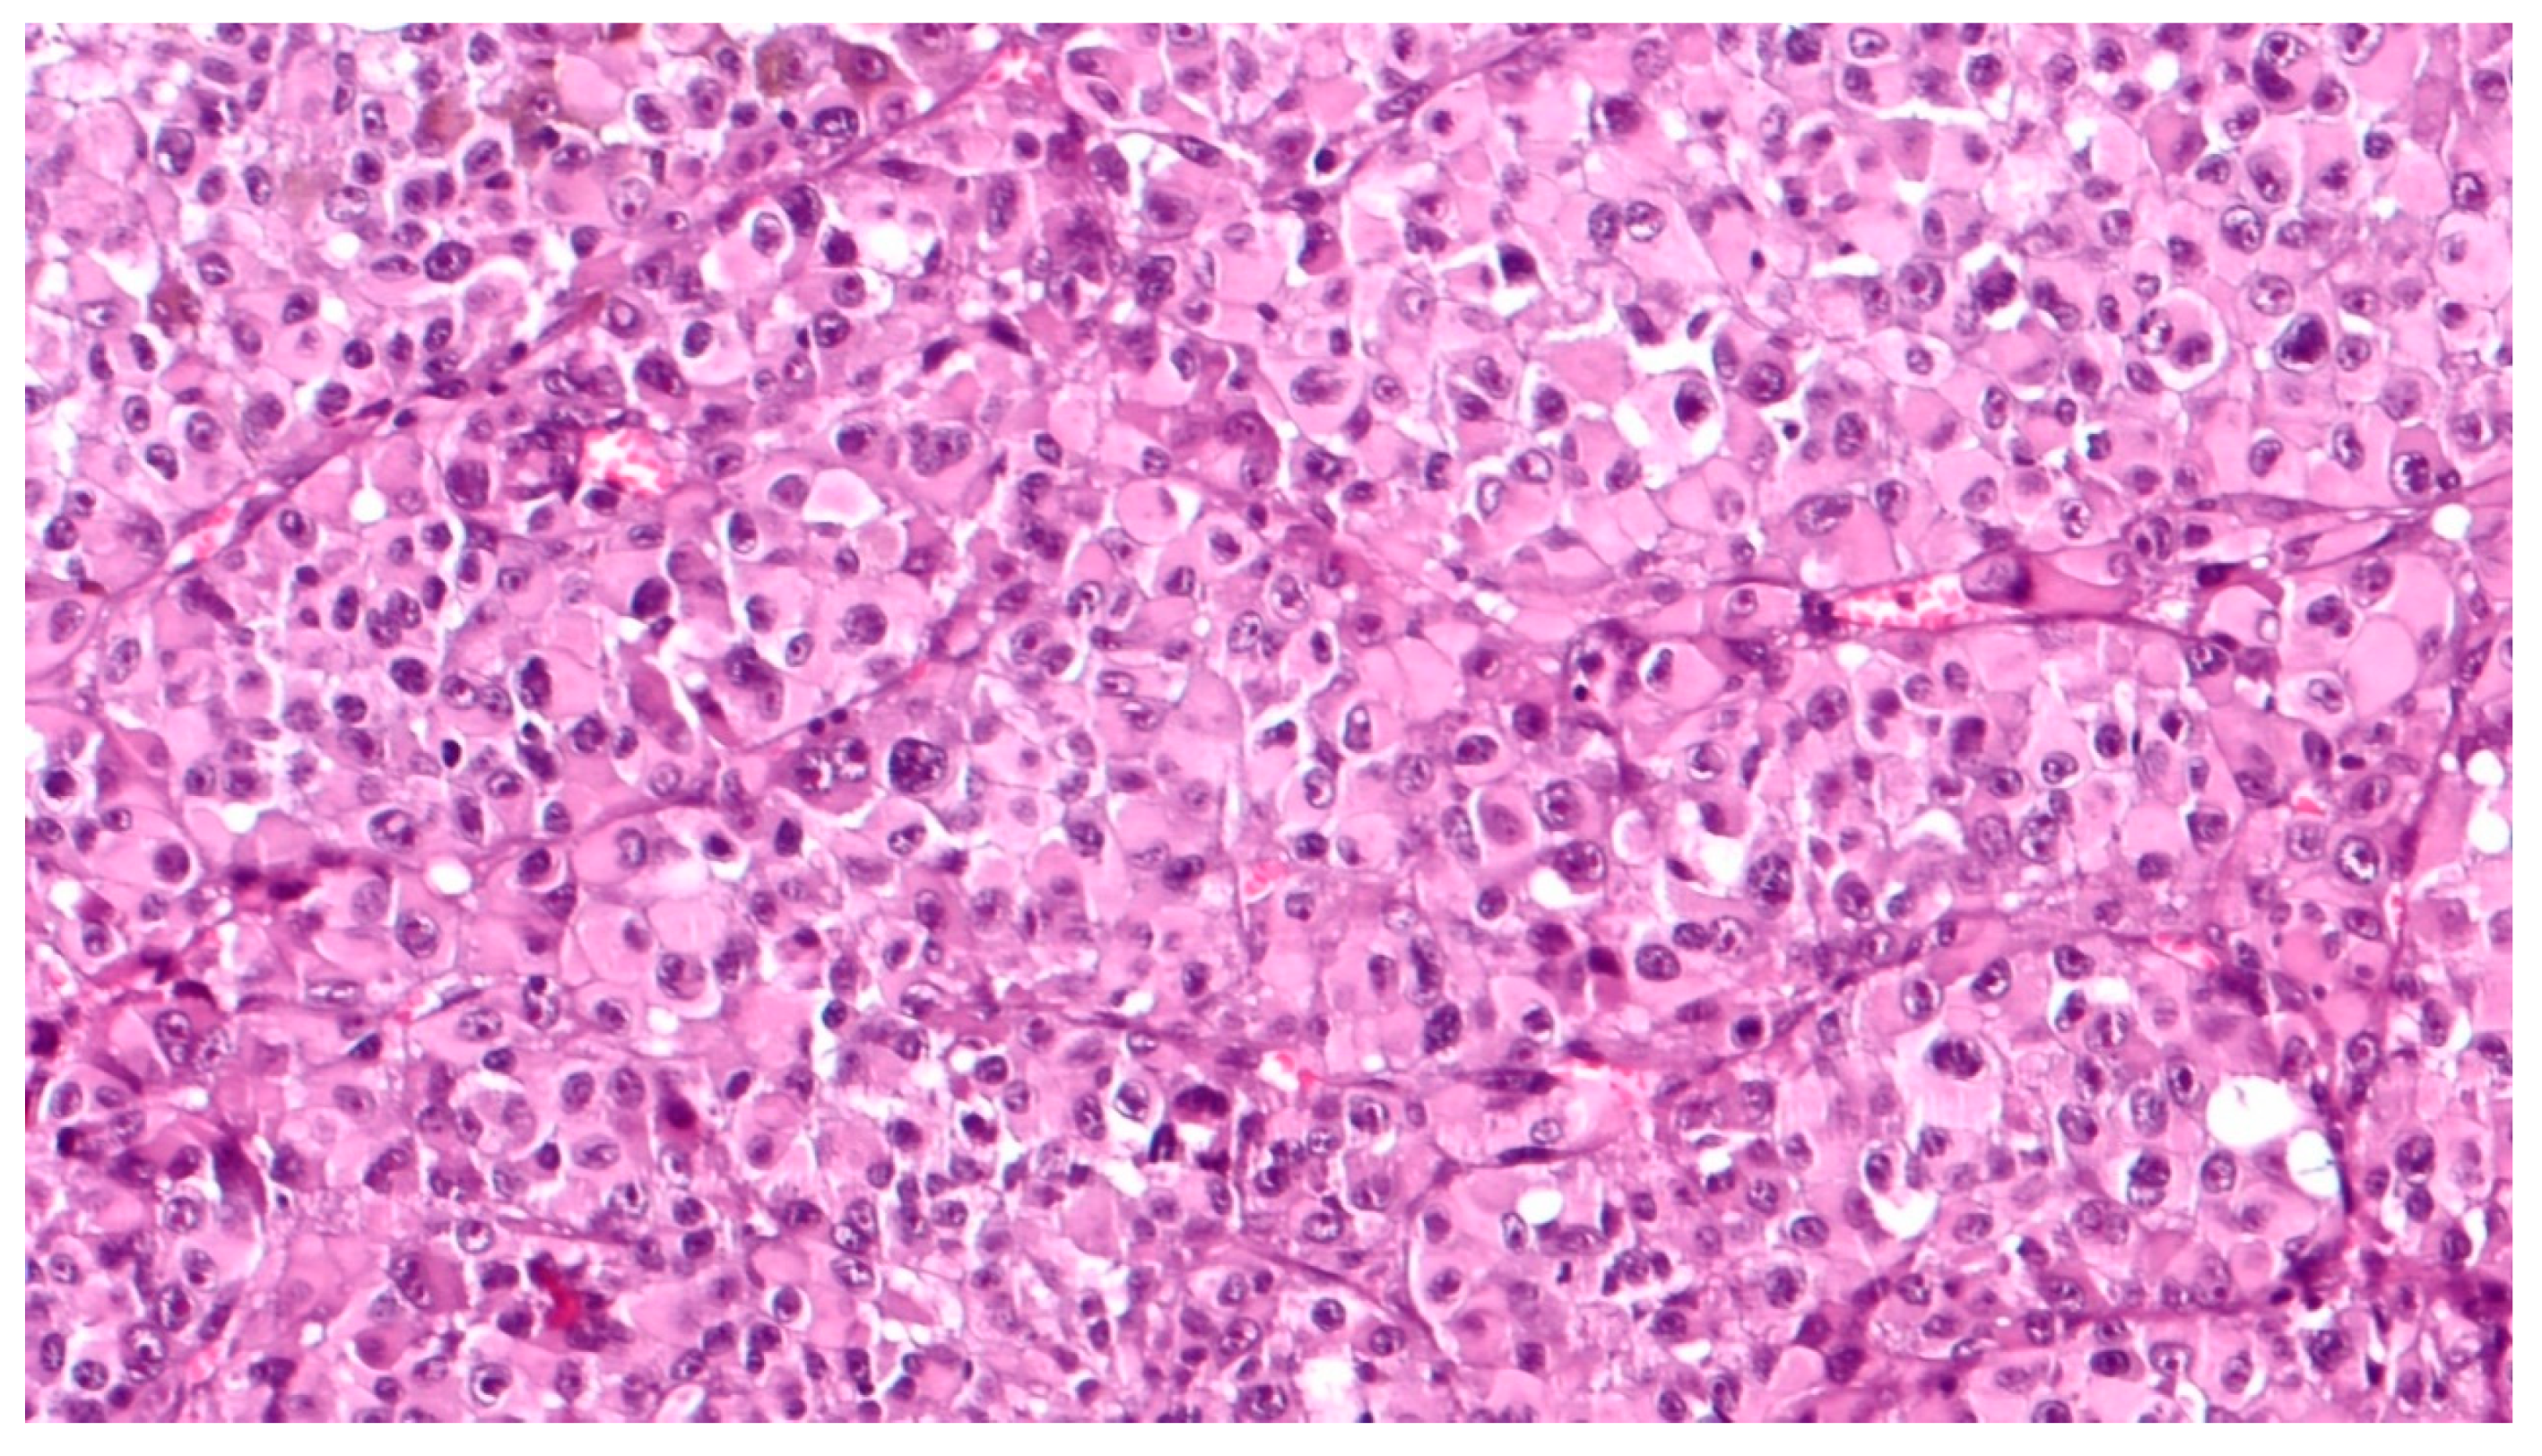

Figure 3.

High magnification showing epithelioid cell type, poorly pigmented, choroidal melanoma, composed of polygonal cells with abundant, eosinophilic cytoplasm, distinct cell borders and large nuclei with conspicuous nucleoli (hematoxylin and eosin; original magnification 200×).